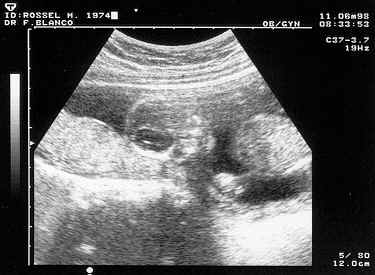

Cette échographie effectuée le 11 juin 98 (presque 4 mois) montre la tête, le haut du corps et le bras gauche. On dirait qu'il dort, couché sur le ventre, la tête nous faisant face semble posée sur un oreiller qui est en fait le placenta. On distingue le haut du corps ainsi que le bras gauche (sur la droite de l'image) qui est replié le long du corps. La main ne se trouvant pas loin de la bouche.